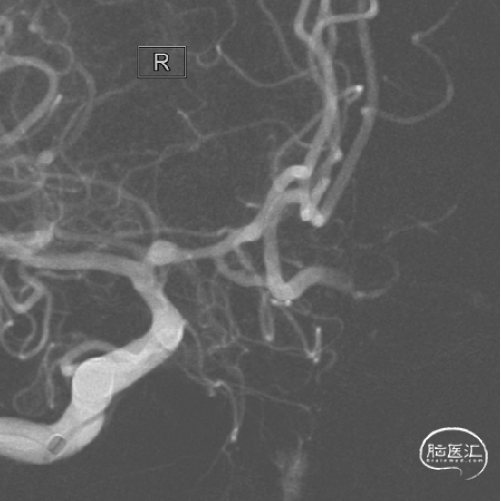

影像学检查:

2024年03月27日在局麻下行DSA检查。

右侧颈内动脉造影

左侧颈内动脉造影

1.该患者动脉瘤虽然是未破裂动脉瘤,动脉瘤不大;但动脉瘤为多发,且形态不规则,存在破裂出血风险,故建议患者积极处理。

2.对于A1起始部动脉瘤的介入治疗,栓塞微导管从同侧颈内动脉入路,微导管塑形较困难,而且手术过程中微导管到位困难以及稳定性也差;栓塞微导管从对侧到位是一个好选择,但术前评估A1与动脉瘤关系非常重要。

3.该患者双侧动脉瘤的栓塞微导管均是从对侧入路到位,也就是“左右开弓”;该患者双侧股动脉置鞘,栓塞微导管从对侧颈内动脉经前交通动脉到达对侧A1动脉瘤,行程路径长,所以每一步操作要谨慎,术中出现了载瘤动脉急性闭塞并发症,术者快速判断及果断处理非常重要,也就是“步步为营”;最终手术顺利完成,患者术后恢复良好,包括术后半年复查动脉瘤栓塞满意,终获“左右逢源”。